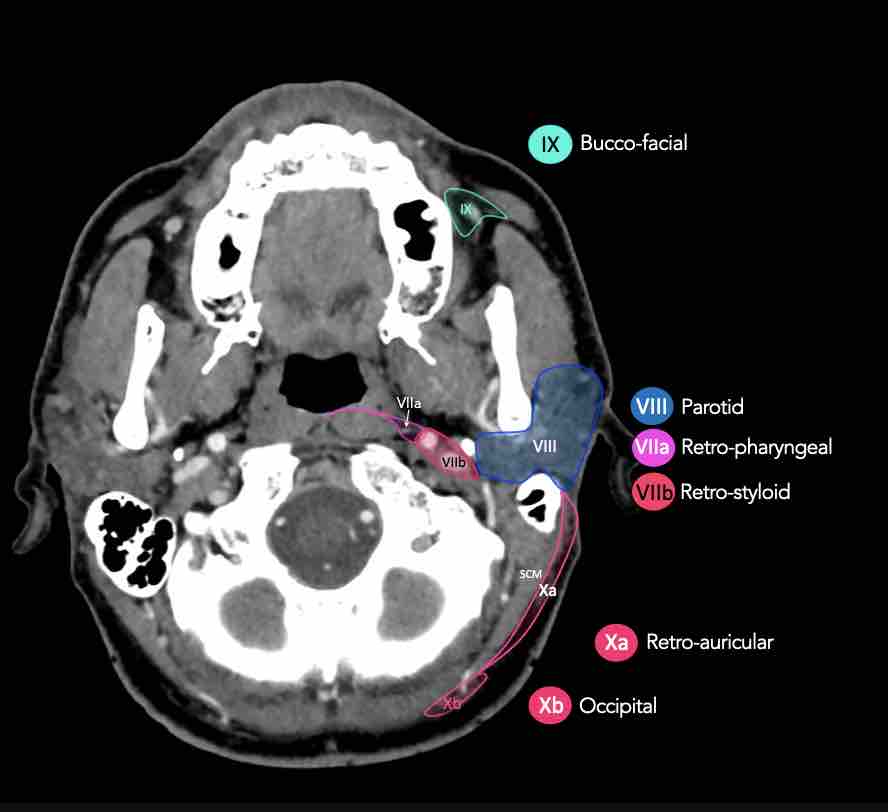

CT Scan Mặt Cắt Ngang (Axial CT)

Các lát cắt CT mặt phẳng ngang tương ứng với hình minh họa tổng quan.

Các lát cắt CT mặt phẳng ngang với hình ảnh chi tiết hơn.

Nhấp vào hình ảnh để phóng to.